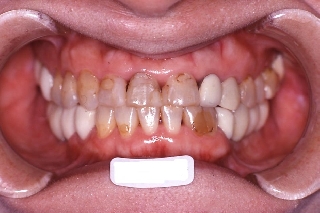

インプラント治療の為の矯正治療症例1

初診時年齢58歳。下顎臼歯部インプラント治療前の咬合改善を目的に来院。

咬み合わせを高くする事で受け口の改善ならびに下顎インプラント挿入スペースを作成した。

矯正治療と並行して専門医によるインプラント治療を行った。

治療前 治療後

正面 正面 正面